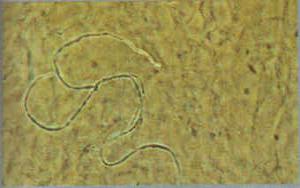

柱顶孢霉感染